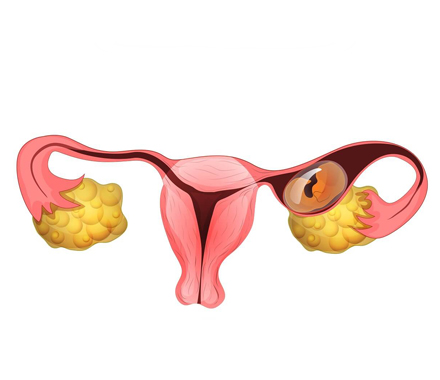

Ectopic Pregnancy

Ectopic pregnancy is a serious condition that occurs when a fertilized........

Ectopic Pregnancy